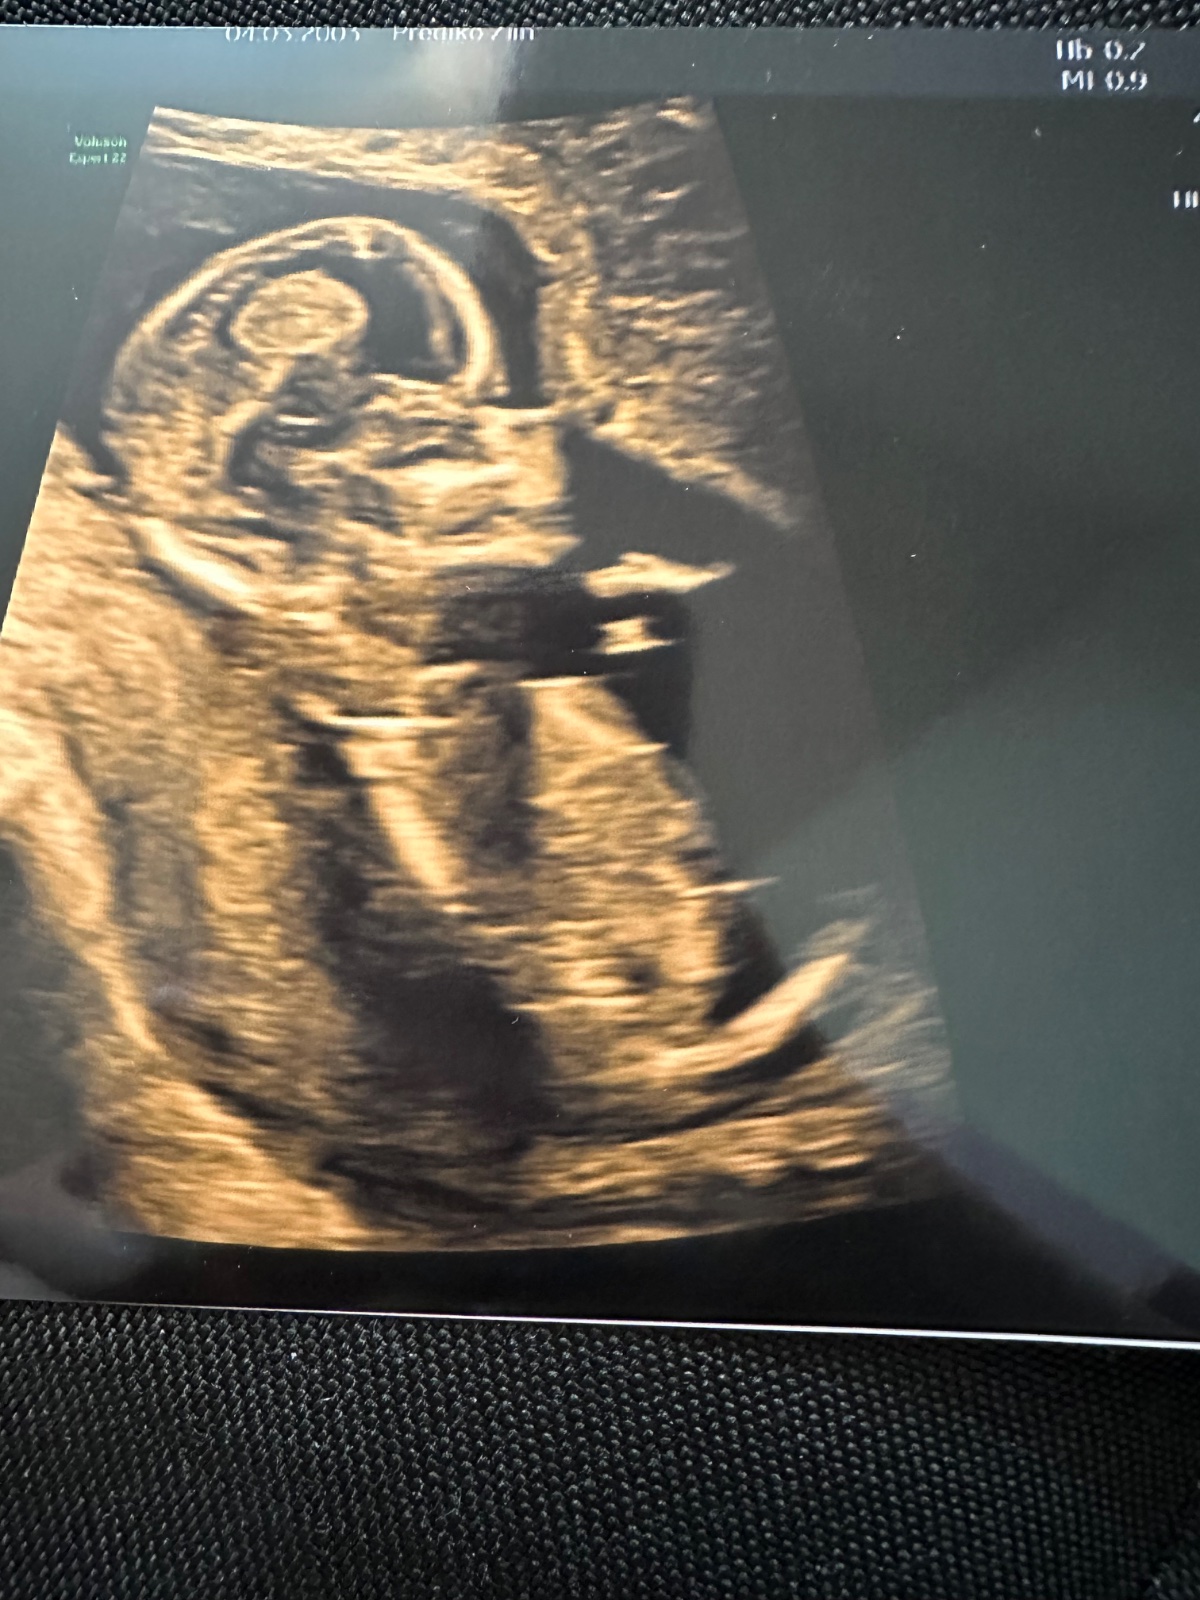

jsem v půlce 4. měsíce a chtěla bych se zeptat, zda jde z ultrazvuku odhadnout, jestli je to chlapeček nebo holčička.

z fotografie bohužel nic říci nelze...